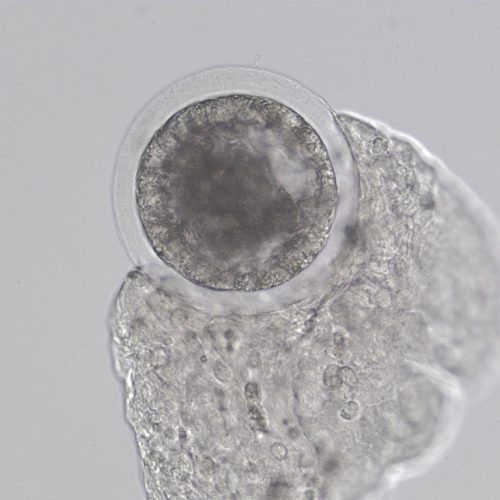

- Capsule: The embryonic capsule is unique among domestic mammals. This is a glycoprotein protective coat formed by the trophoblast layer beneath the zona pellucida. It forms only after the embryo enters the uterus, so embryos grown in a laboratory do not develop the capsule until after they are transferred. If not protected by either the zona pellucida or the embryo capsule, an embryo cannot survive in the uterus.

- Growth rate: Once the embryo becomes a blastocyst and starts expanding around day seven, the embryo will nearly double in size each day until day 12. This allows early ultrasound determination of pregnancy status, as an embryo around 300-400 microns (0.3-0.4mm) in size when recovered at day seven will grow to 3-4mm, large enough to be visualized on an ultrasound scan, by day 11.